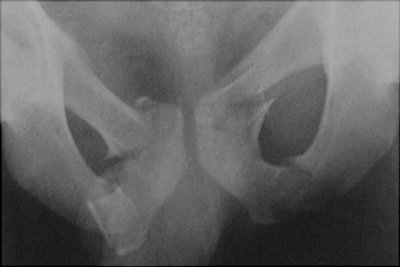

Return to Straddle Injury